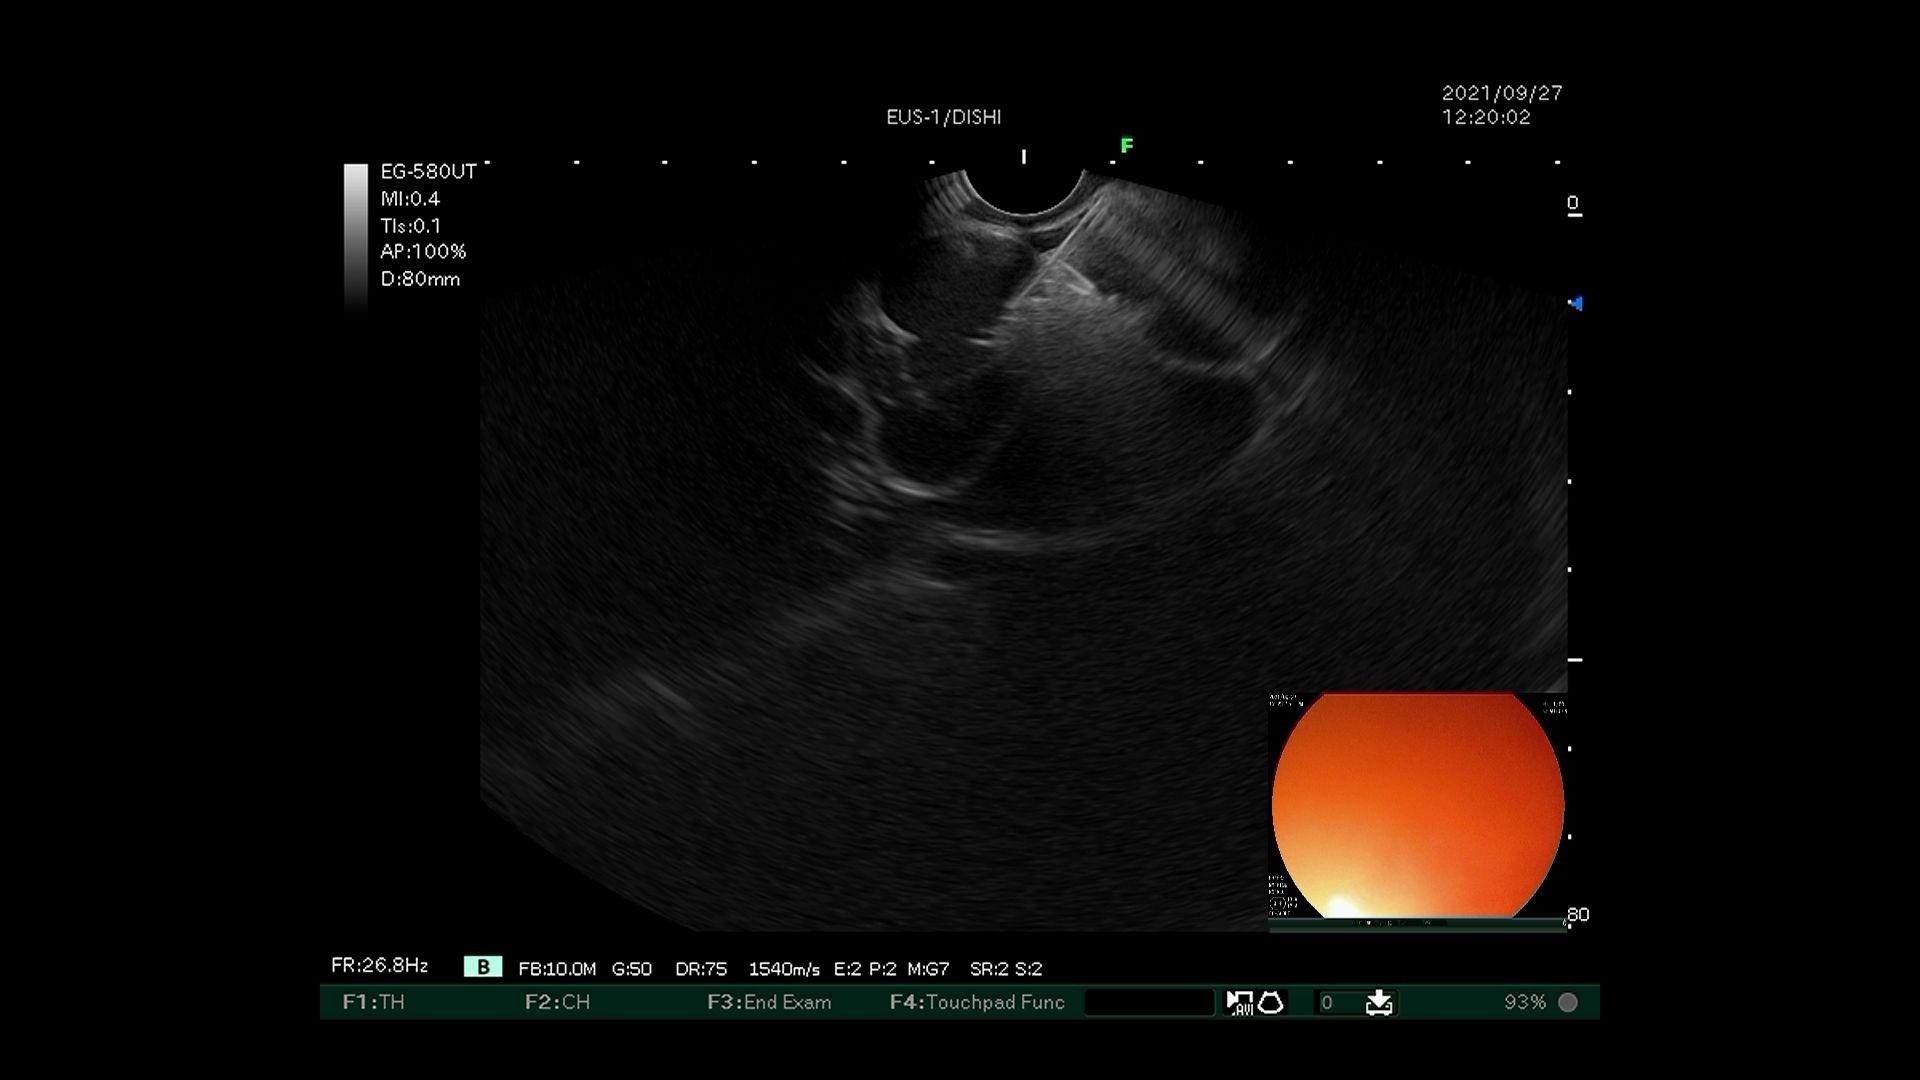

4)EUS引导下穿刺针进入内径最宽的曲张静脉置入弹簧圈。

超声内镜引导下弹簧圈置入联合组织胶栓塞术先使用超声内镜识别胃底曲张静脉,选取曲张静脉内径最宽处,在超声内镜引导下经食管下段、膈肌角以19G穿刺针穿入曲张静脉,置入数枚略大于曲张静脉内径的弹簧圈,然后用“高糖-组织胶-高糖”三明治法于曲张静脉内注射组织胶,最后使用超声内镜确认曲张静脉血流信号消失。该技术可明显降低异位栓塞的风险,但需要手术者同时具有超声内镜及静脉曲张两个亚专业的熟练操作技巧,手术大出血风险极高,若有不慎即可导致术中患者死亡。